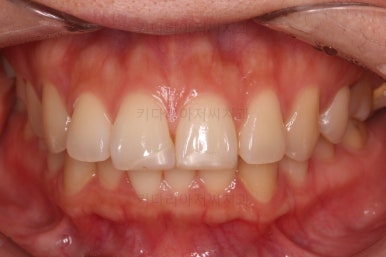

마찬가지로 부산연산동교정치과 초진 시 입안의 모습입니다.

눈에 띄는 것은 윗니 안쪽 치아 하나가 아예 입천장쪽으로 나서 매우 삐뚤어요.

아래 앞니도 삐뚤한 편이었고 아래 앞니가 불쑥 위로 올라와 있어서 이를 악 다물면 위아래 앞니가 많이 겹치는 "과개교합" 패턴이 나타나요.

윗니가 전반적으로 아랫니보다 앞에 나와 있어서 2급 부정교합에 윗니만 튀어나온 양상이고 이 때문에 윗니 앞니가 다치고 부러졌따가 떼운 흔적이 보이네요.